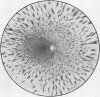

Intermediate sex-linked inheritance.